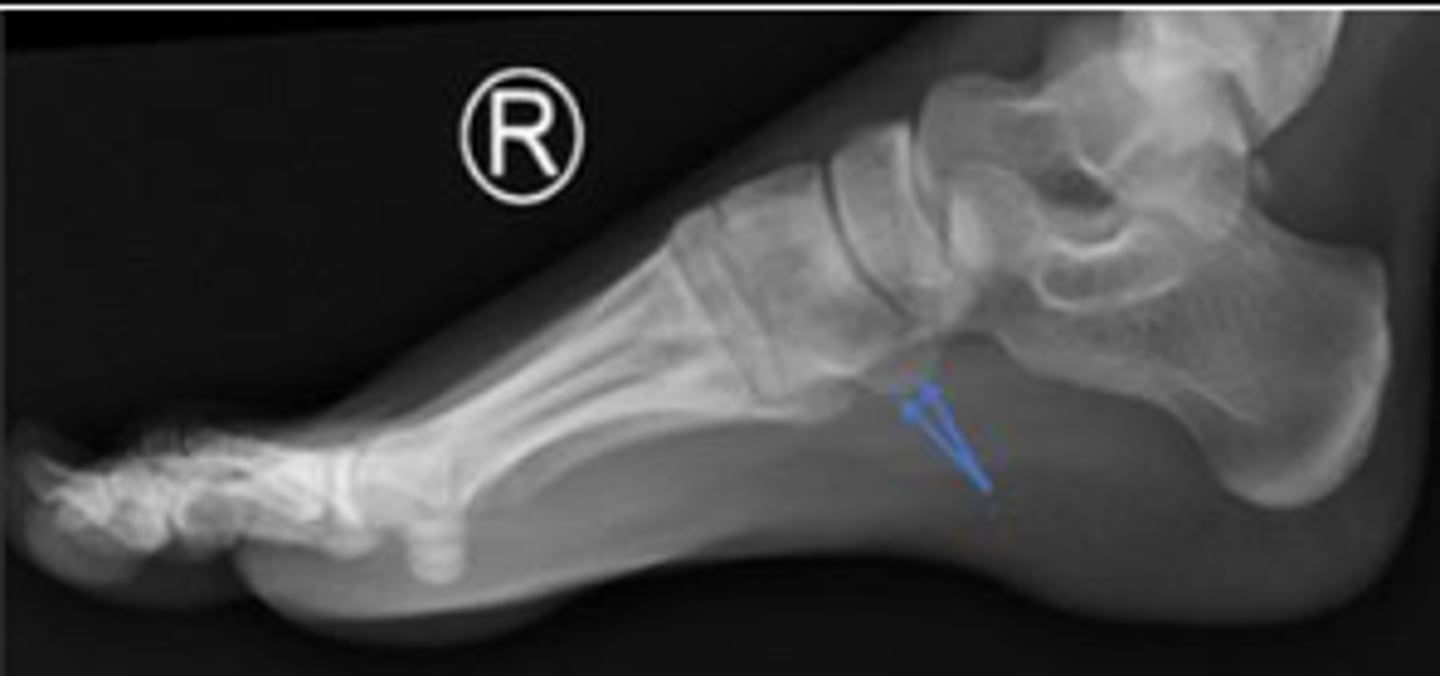

Right lateral foot

What is the name of the radiographic view?

Heel pad measurement

What is the name of the assessment?

Females: average 19mm (maximum of 23mm)

Males: average 19mm (maximum of 25mm)

What is the normal range for the assessment?

Achille's tendon thickness

4-8mm

Yes

Is the assessment within normal limits?